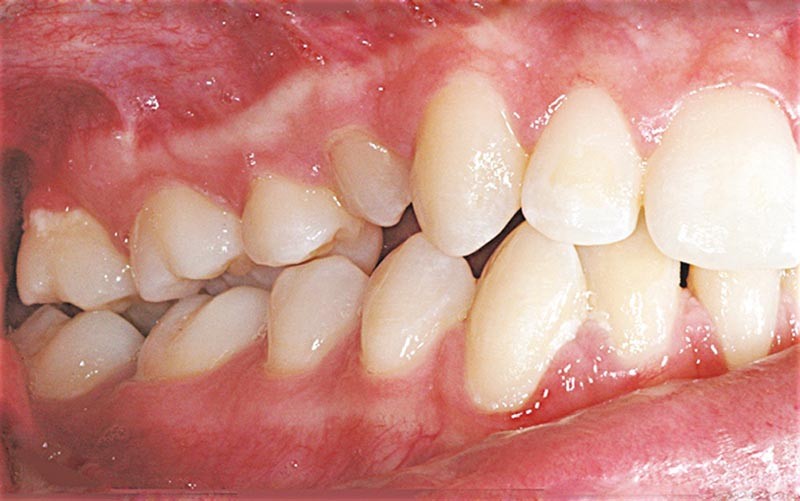

L’atteinte desmodontale, en particulier le risque d’ankylose, constitue un facteur limitant pour l’orthodontie. En effet, le déplacement orthodontique d’une dent dépourvue de desmodonte est tout simplement inconcevable sur le plan histologique ; sans compter les effets parasites engendrés au niveau des dents voisines (fig. 1).